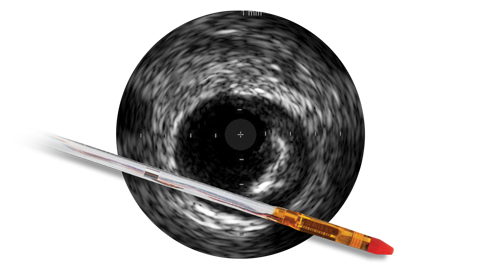

Ангиография дает сведения о характеристиках просвета сосуда, но не позволяет получить четкого изображения сосуда и поражения.

Между тем, использование ВСУЗИ помогает получить более четкую картину и улучшить результаты лечения пациента за счет планирования стентирования на основе данных и оптимизации стента после его установки1.